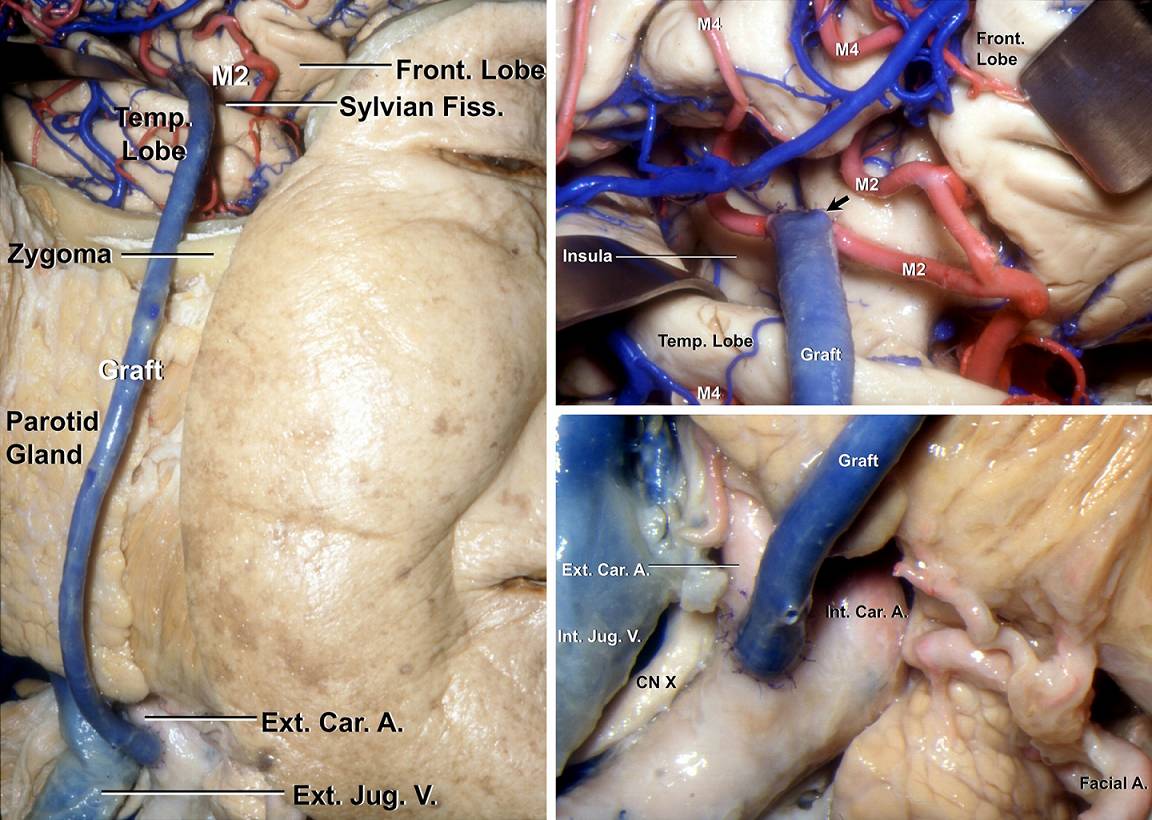

图2. 尸头标本演示使用静脉进行ECA/ICA-M2高流量搭桥。颧弓上钻一沟槽容纳桥血管无缠结地通过;在豆纹动脉远端选取一段分支最少的M2作为受血动脉临时阻断,采用端-侧吻合的方式以8-0或9-0的尼龙线间断缝合远端吻合口(右上图的箭头);随后完全阻断颈部的ICA或ECA,使用7-0尼龙线,桥血管近端可以端-侧吻合至ICA,也可以端-端吻合至ECA。(图片由AL Rhoton,Jr教授授权)